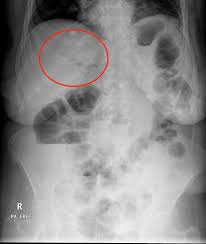

Do Kidney Stones Always Show On X Ray. Your radiologist will view the images and interpret the results. Ct scans use a combination of x rays and computer technology to create images of your urinary tract.

Not all stones are visible on abdominal x ray. Imaging tests can help tell your doctor how big it is and exactly where it s located. Results of a kub study may show injuries to your stomach or intestines.

Ct can identify tiny kidney stones and more importantly can determine whether there is obstruction. A plain x ray will only see kidney stones that have partially calcified. X ray results are usually available within a few minutes. All kinds of kidney stones show up on the ultrasound though.